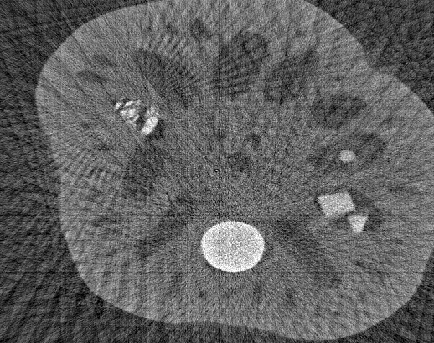

We implemented the methods 1 and 2 in Matlab and tested them on the x-ray CT data of a lotus root, cf. [7]. In our experiments we converted the fan-beam data to a parallel-beam data using Matlab function fan2para and downsampled this data in order to simulate angular undersampling. Thereby, we used 738 equispaced samples in the s𝑠s-variable and 363636 evenly distributed angles in [0,π)0𝜋[0,\pi). For our implementations, we used the Matlab functions radon and iradon as numerical realizations of the Radon transform, the inverse Radon transform and the backprojection operator. For the minimization of the 1superscript1\ell^{1}-functional (9), we implemented the iterative soft thresholding algorithm, cf. [8].

The CT data and the corresponding FBP reconstruction are shown in Fig. 1(a) and 1(d). It can be clearly observed that the FBP reconstruction contains many undersampling artifacts (streaks) that could complicate the detection of edges in that image. Hence, we calculated the gradient directly from CT data using the methods 1 and 2, where we chose the parameters based on visual inspection of edge detection results. These are given in the caption of Fig. 1.

Figure 1: Rebinned CT data of a lotus root 1(a) and the corresponding FBP reconstruction 1(d) from an angular range given by [0,π)0𝜋[0,\pi) and 363636 evenly distributed angles, cf. [7]. The magnitude of the gradient |fε|subscript𝑓𝜀\left|\nabla f_{\varepsilon}\right|, in 1(b) and 1(c), and the corresponding edge detection results using the Canny algorithm, see 1(e) and 1(f).

In Fig. 1(b) and 1(e) one can see that the Gaussian smoothing cannot compensate for the undersampling artifacts and, thus, many edges in the edge map are not coming from actual image features. However, the 1superscript1\ell^{1}-regularization successfully reduces the number of artifacts and detects the edges more reliably, as can be seen in Fig. 1(c) and 1(f). In other experiments we also observed that the method 2 outperforms the method 1 whenever the CT data was not sampled properly. For dense angular sampling, we found that both methods produce similar edge detection results.